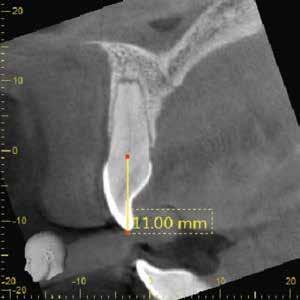

Egy 38 éves nőbeteg a korábban kezelt jobb felső második kisőrlőfogából (1.5) kiinduló mérsékelt fájdalom miatt jelentkezett rendelésünkön. A kórtörténetében jelen panasza szempontjából releváns információ nem szerepelt. A beteg a klinikai vizsgálat során vertikális kopogtatásra enyhe érzékenységet jelzett. A kérdéses fog körül mérhető szondázási mélység és a fogmobilitás fiziológiás volt. Periapicalis röntgenfelvételen egy, a fog gyökércsúcsán túl presszálódott betört gyökérkezelő műszerből származó eszközfragmentumot láttunk (2. a. ábra). A preoperatív CBCT-felvétel a buccalis csontlemez épségét igazolta (2. b-c. ábra). A fog revíziója öt hónappal korábban történt. A már előzőleg gyökérkezelt, gyökértömött, majd revideált 1.5-ös fog esetében a diagnózisunk periodontitis periapicalis symptomatica volt. A periapikális elváltozás kezelése érdekében navigált endodonciai mikrosebészeti beavatkozást végeztünk.

A felső állcsontról intraorális szkent (TRIOS) készítettünk, és az ezáltal kapott STL fájlt (2. d. ábra) a CBCT-felvétel során nyert DICOM fájlokkal a Zirkonzahn.Implant-Planner (Zirkonzahn) szoftverben egyesítettük. A sebészi sablont ebben a programban megterveztük, majd a Meshmixer (Autodesk) szoftver se-

gítségével tovább módosítottuk. Az így kapott sebészi sablon egyértelműen meghatározta a periapikális terület eléréséhez szükséges csontablak határait (2. e-f. ábra) Helyi érzéstelenítést követően teljes vastagságú mucoperiostealis lebenyt képeztünk, majd a buccalis csont feltárását követően (2. g. ábra) a sablon segítségével bejelöltük a preparálandó csontablak határait (2. h. ábra). A csontablak kialakítása során Piezotome CUBE LED kézi-darabot alkalmaztunk, majd a leemelését követően a betört eszközt megkerestük (2. i. ábra) és eltávolítottuk (2. j. ábra). A rezekciót ultrahangos megmunkáló fejekkel (ACTEON) végeztük, majd retrográd preparáció következett.

A retrográd gyökértömés elkészítése során TotalFill BC RRM Fast Set Putty-t (FKG) használtunk (2. k. ábra). A lebeny széleit 5/0-s Prolene varratokkal egyesítettük (2. l. ábra). A varratok a műtétet követően 72 órával kerültek eltávolításra. A beteg két évvel később kontrollröntgen készítése céljából érkezett rendelőnkbe. A vizsgálat során a fog tünetmentesnek és funkcióképesnek bizonyult (2. m. ábra).